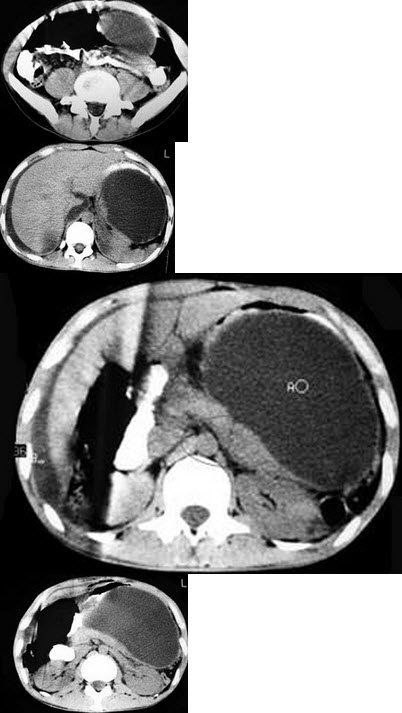

男,33岁,腹部外伤后两月余,腹部疼痛,行CT扫描所见如图,最可能的诊断是( )

A:急性胰腺炎

B:慢性胰腺炎

C:胰腺创伤性假性囊肿

D:畸胎瘤

E:腹腔包裹性积血